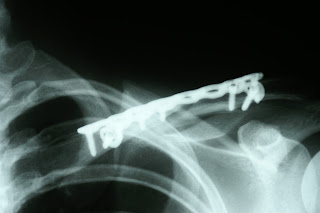

That, my friends, is a picture of a real live human shoulder in the middle of a surgical procedure called "open reduction internal fixation" or ORIF. This patient broke his collarbone, and the break was bad enough to need surgery to put it all back into place (the x-ray below is also a great example of a break that will need internal fixation of some sort). That teal plate that is sitting on the bone, is what the surgeon uses to put the bone back into place and hold it there. I was involved in the design of that plate.

Yup, I designed that plate too :)